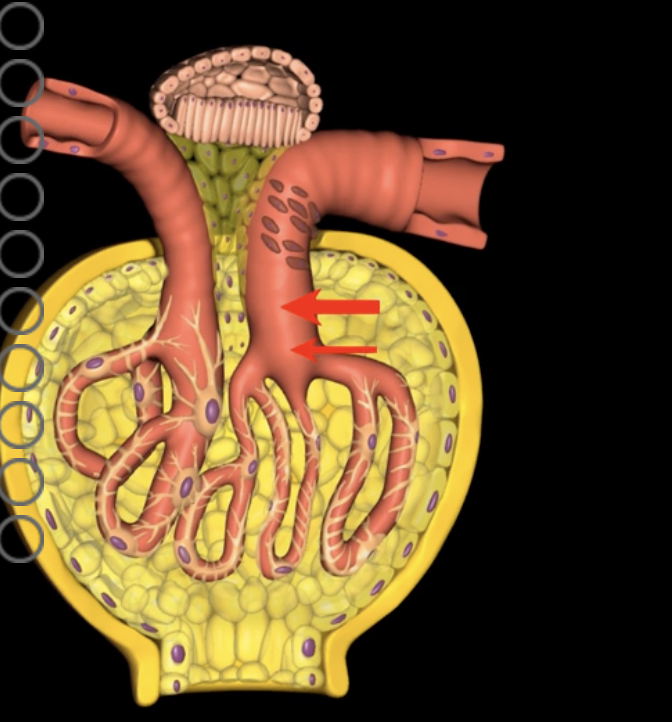

which decreases HPg and GFR, and causes decreased urine volume

Vasoconstriction of the afferent arteriole decreases blood flow into the glomerulus…..

which also decreased HPg and GFR, causing decreased urine volume

Vasodilation of the efferent arteriole increases flow out of the glomerulus…

macula densa cells stimulate afferent arteriole vasoconstriction to reduce GFR, slowing filtrate flow and optimizing reabsorption

high concentrations of Na+ and Cl- in the filtrate indicate high flow rate with decreased reabsorption. causing?